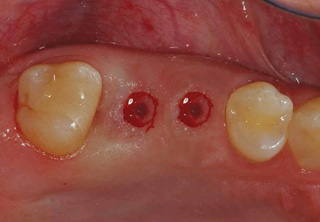

치조골이식술

임플란트의 성공률 UP!

골이식 임플란트

치조골 이식술이란?

치주염 등으로 치조골(잇몸뼈)의 양이 부족한 경우

치조골 이식술을 통하여 충분한 뼈의 양을 확보한 후

임플란트를 식립합니다.

뼈의 밀도가 치밀하고 단단하며, 양이 충분할수록 임플란트의 성공률이 높아집니다.

청담네오플란트는 풍부한 경험의 의료진이 치조골 이식술을 통해 치조골을 적절한 양과

밀도로 재생시킨 후 임플란트를 식립합니다. 뼈의 흡수가 심하지 않아 적은 양의

치조골 이식을 하는 경우 임플란트 식립을 동시에 진행할 수 있지만, 뼈의 흡수가

심하여 많은 양의 치조골 이식이 필요한 경우 치조골 이식술을 먼저 진행한 후,

치조골이 재생되면 임플란트를 식립하여 보다 정밀하고 안전한 시술 결과를 얻을 수 있습니다.

치조골 이식술 전후사진